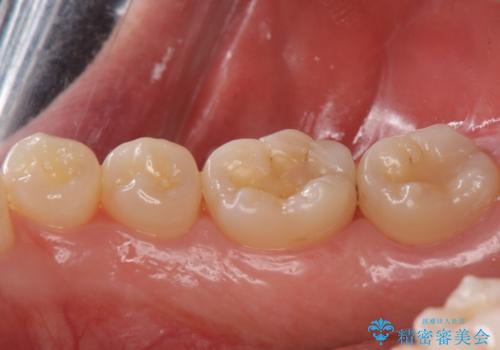

虫歯が大きくなりきる前に治療を行えたため、歯の削る量を抑えることができました。

精度の良い詰め物は今後の虫歯リスクを抑えることにもつながります。